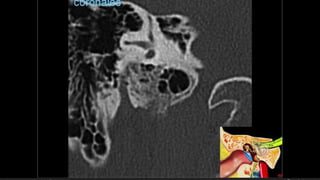

Evaluación Imagenologica

• #52 AXIAL Frctua canal carotideo